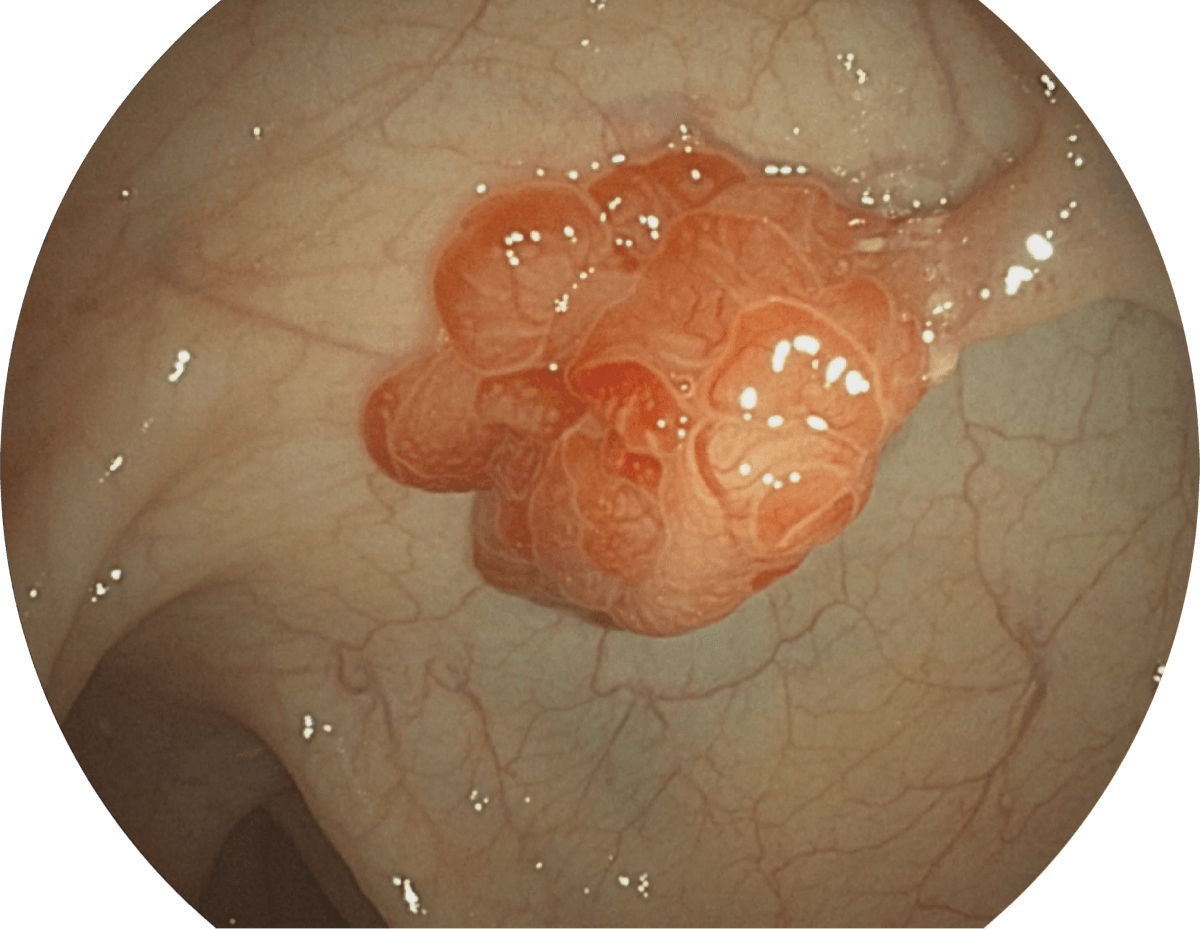

具有聚谱成像技术(SFI)及光电复合染色成像技术(VIST),可完美呈现粘膜细节及病变特征。

(Spectral Focused lmaging, SFI)

( Versatile Intelligent Staining Technology, VIST )

WL

SFI

VIST